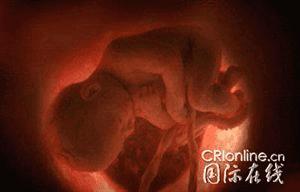

母亲子宫内10周大的胎儿

母亲子宫内28周大的胎儿